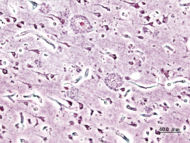

| Histopathologic image of senile plaques seen in the cerebral cortex in a patient with Alzheimer disease of presenile onset. Silver impregnation. | |

Both amyloid plaques and neurofibrillary tangles are clearly visible by microscopy in AD brains. Plaques are dense, mostly insoluble deposits of amyloid-beta protein and cellular material outside and around neurons that build up to insoluble twisted fibers within the nerve cell, often called tangles. Though many older people develop some plaques and tangles, the brains of AD patients have them to a much greater extent and in different brain locations.

Alzheimer's disease has been identified as a protein misfolding disease, or proteopathy, due to the accumulation of abnormally folded A-beta and tau proteins in the brains of AD patients. Plaques are made up of small peptides (39 to 43 amino acid residues each) called beta-amyloid (also written as A-beta or Aβ), a protein fragment from a larger protein called amyloid precursor protein (APP). APP is a transmembrane protein, which sticks through the neuron's membrane, and helps neurons grow, survive and repair themselves after injury. In AD, an unknown process causes APP to be divided into smaller fragments by enzymes through proteolysis. One of these fragments is beta-amyloid, or amyloid fibrils, which form clumps that deposit outside neurons in dense formations known as senile plaques.